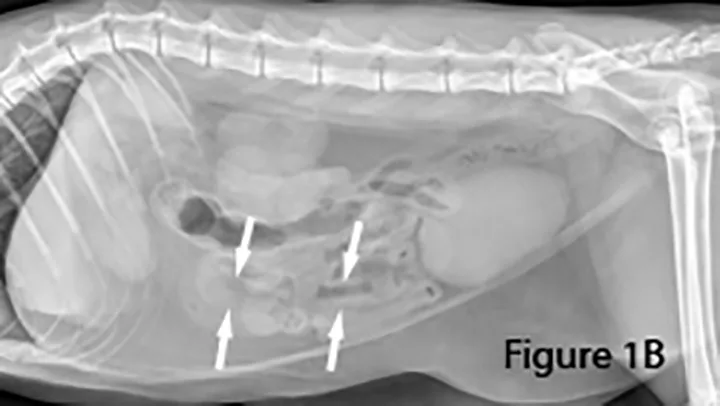

Lateral abdominal radiograph of a dog with small intestinal obstruction. There is marked segmental small intestinal dilation (arrows) with heterogeneous soft tissue and mineral opaque material in the lumen. The cause (ie, the mass) is not identifiable radiographically; there is a large amount of normal empty small intestine.